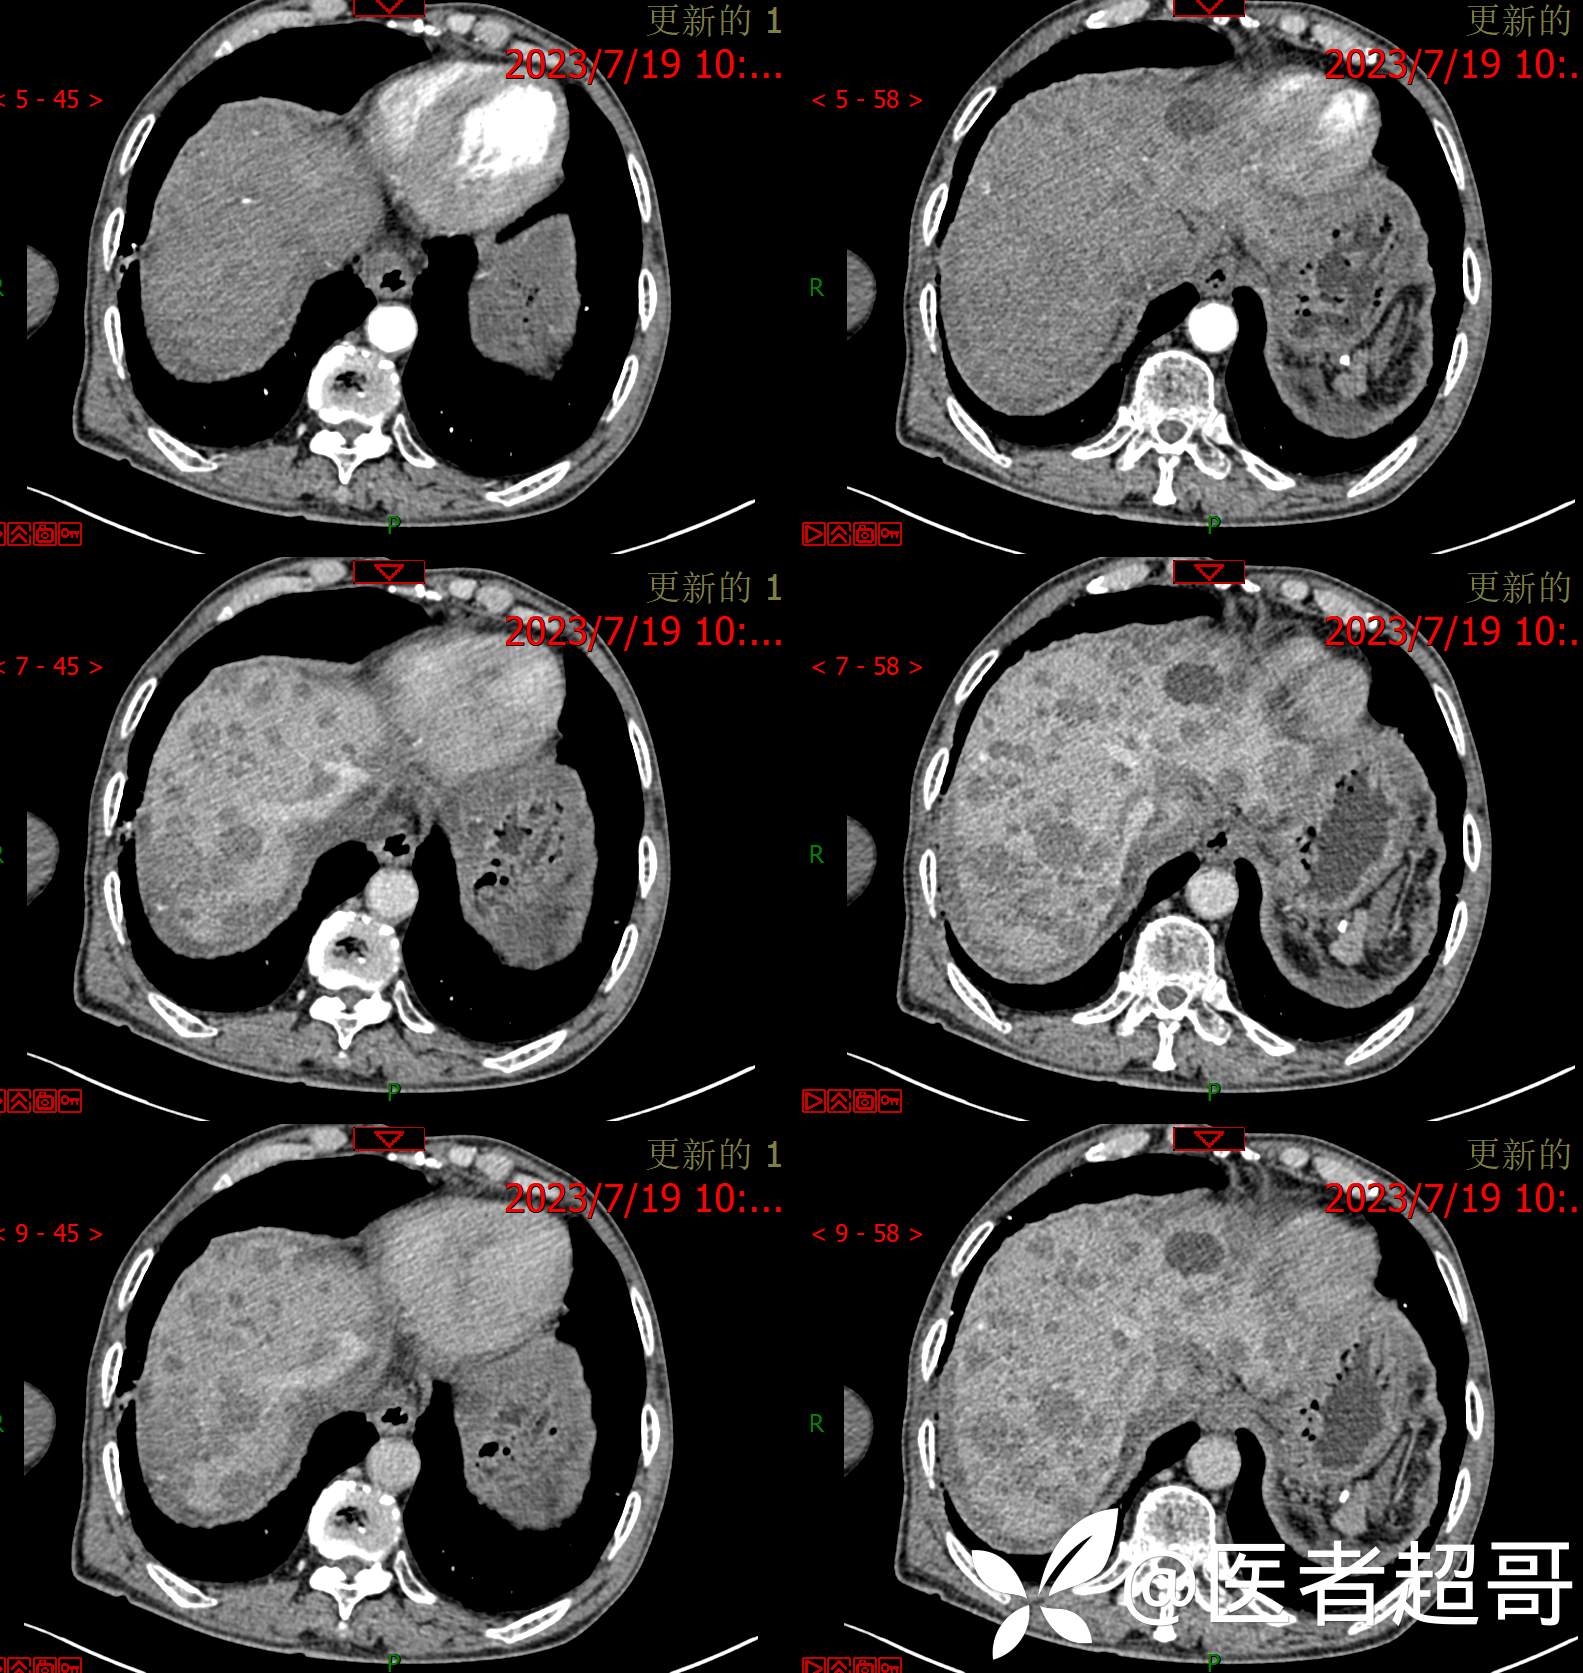

术后三个月复查CT、MRI表现:

转移性肝癌 (39)